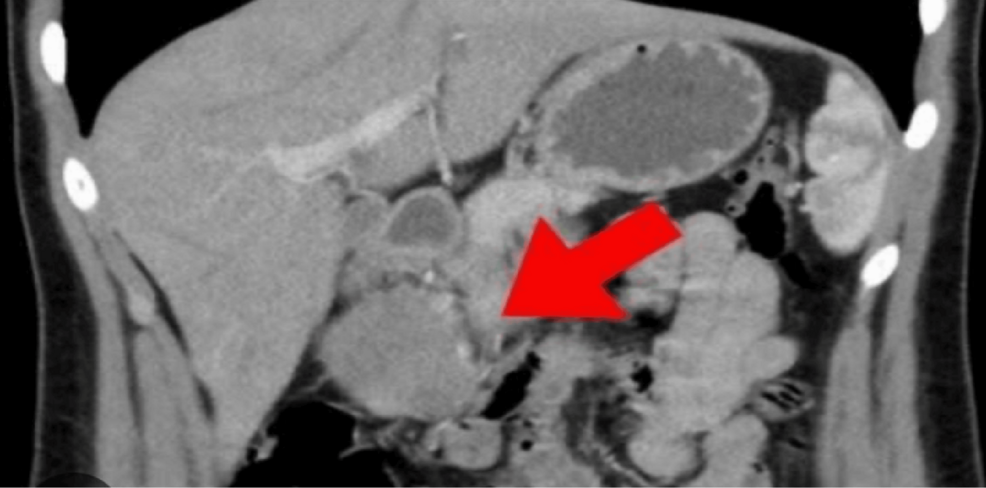

The Frantz tumor, first described by Frantz in 1959, is generally considered to be an indolent, or slow-growing, tumor. However, it can still present with significant symptoms, such as abdominal pain. The case report details a 60-year-old female patient who presented with occasional abdominal pain. Imaging studies, including positron emission tomography/computed tomography (PET/CT) and magnetic resonance imaging (MRI), revealed a mass in the tail of her pancreas.

Diagnosing SPNs can be complex. The imaging differential diagnosis can include other pancreatic cysts and tumors, such as complicated pancreatic pseudocysts, hydatid cysts, and mucinous cystic neoplasms. This complexity is underscored by the initial misdiagnosis in the reported case, where the tumor was initially suspected to be an infected pseudocyst.